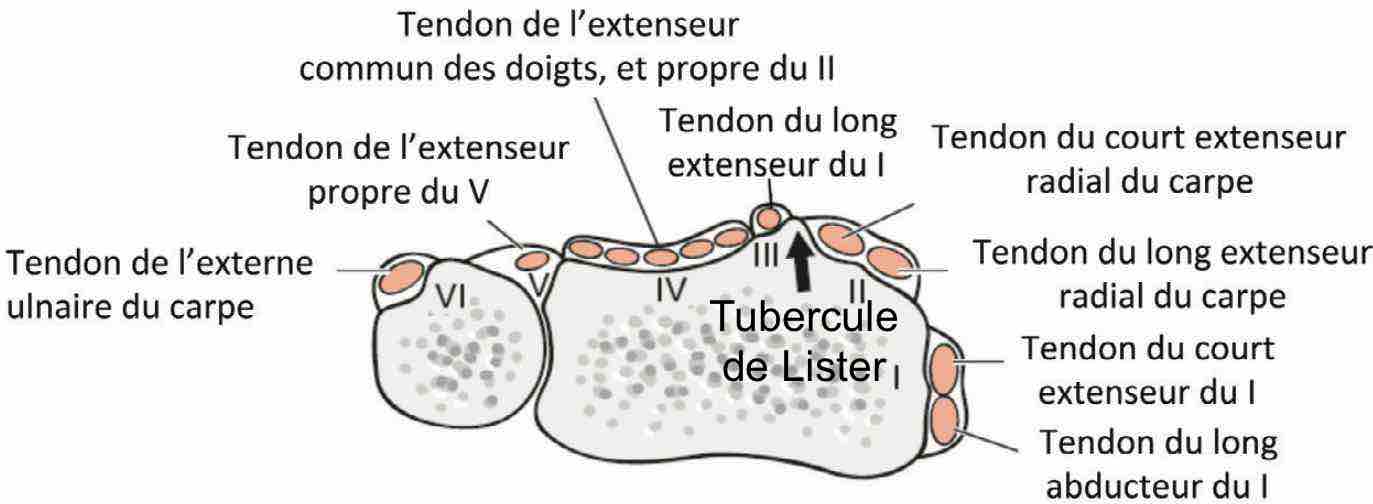

Pas d'épanchement dans les articulations radiocarpienne, radioulnaire distale et médiocarpienne.

Pas d'anomalie décelable des tendons extenseurs et fléchisseurs.

De Quervain

Epaississement rétinaculaire supérieur à 1 mm autour du premier compartiment des extenseurs.

Aspect hypoéchogène. Hyperhémie associée. Douleurs reproduites au passage de la sonde.

Pas d'anomalie des tendons du court extenseur et du long abducteur du pouce.

Pas d'éperon osseux ni de septum intertendineux.

sd canal carpien = nerf > 12-15 mm², index d'aplatissement > 3,

sd canal carpien = nerf > 12-15 mm², index d'aplatissement > 3,nerf hypo +/- signal Doppler, bombement rétinaculum > 4 mm,